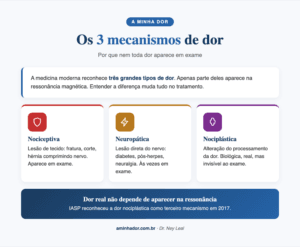

Persiste por mais de 12 semanas. Nesse ponto, a dor não é mais apenas um sintoma, ela se tornou uma condição em si. O sistema nervoso pode estar sensibilizado, amplificando sinais que antes não eram sentidos como dor. É quando o tratamento multidisciplinar faz mais diferença. Pra entender melhor esse processo, leia nosso guia sobre o que é dor crônica.

Diagnóstico: por que o exame não conta a história toda

Na maioria dos casos, o diagnóstico da lombalgia é clínico, feito pela conversa e pelo exame físico. Exames de imagem (ressonância, raio-X) são indicados quando há sinais de alerta, quando a dor não melhora depois de 4 a 6 semanas de tratamento, ou quando há suspeita de outra causa específica.

Eu sempre opto por pedir pra paciente me contar primeiro o que está doendo, antes de abrir qualquer exame. E na maior parte das vezes os achados na ressonância não têm nenhuma relação com a dor que ela sente. A gente chama isso de “achado incidental”, são alterações compatíveis com a idade.

Quando o radiologista vê uma imagem pra dar o laudo, ele deve descrever absolutamente tudo o que está vendo. Mas nem sempre o que aparece descrito tem significado clínico ou explica a dor do paciente.

É como se eu pedisse pra alguém descrever uma foto 3×4 minha. A pessoa vai descrever rugas, cabelo e barba com fios brancos, mesmo que isso não tenha significado nenhum, seja absolutamente normal do envelhecimento. Na coluna acontece a mesma coisa, e a gente chama de “degenerações compatíveis com a idade”.

O que a ciência confirma

Não é achismo meu. Uma revisão sistemática analisou exames de imagem da coluna em pessoas sem nenhuma dor e encontrou alta prevalência de “achados” como degeneração discal, protrusões e bicos de papagaio, em todas as faixas etárias[4]. Em pessoas de 50 anos sem sintoma algum, 80% têm degeneração de disco na ressonância. Aos 80 anos, é 96%.

Outro estudo, esse randomizado, dividiu pacientes com lombalgia aguda em dois grupos: um recebeu o resultado da ressonância em 48 horas, o outro ficou cego ao laudo. Resultado: receber o laudo não melhorou o desfecho clínico e foi associado a uma pior sensação de bem-estar[5]. Ou seja, saber em detalhes o que aparece no exame, quando aquilo não muda a conduta, pode até atrapalhar a recuperação.

Por isso, tratar a imagem em vez do paciente é um dos erros mais comuns na abordagem da lombalgia. O diagnóstico bom começa ouvindo a história, não abrindo o envelope da ressonância.